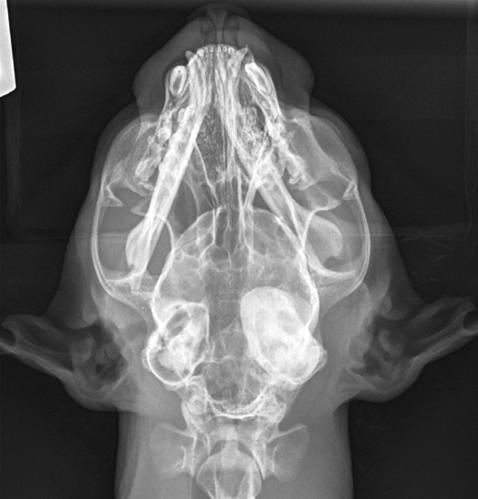

1. Radiografías de la cabeza de un gato maine coon de un año de edad. (A) Proyección lateral. (B) Proyección dorsoventral. (C) Rostro 10º ventrodorsocaudal oblicua.

En la exploración otológica se visualizó una masa en el conducto auditivo externo izquierdo, apreciable desde la abertura del pabellón auricular. La masa era sólida, poco móvil y obstruía totalmente el canal auditivo. El resto del examen físico y pruebas de enfermedades víricas fueron normales. En el análisis sanguíneo se evidenció neutrofilia con desviación a la izquierda y trombocitosis.